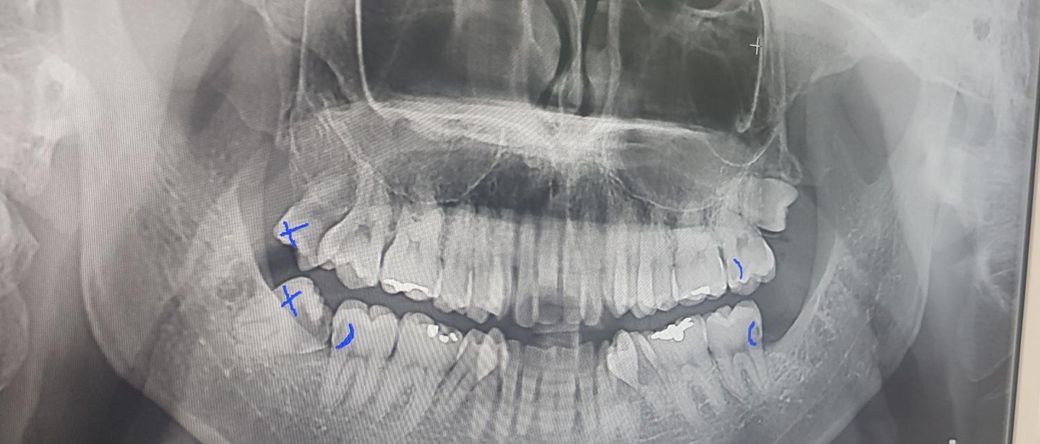

사랑니 때문에 인접면 충치가 생겼는데 신경치료 가능성이 클까요?

47번 어금니 인접면에 충치 때문에

신경치료 해야 할까요?

엑스레이 상으로 치아 사이가 많이 썩어 잇는거 같습니다. 사랑니 때문에 치료를 하는 치아들은 신경치료 가능성이 높아 보이긴합니다.

사진으로 봤을 경우에 충치의 범위가 넓어 보입니다. 충치를 제거했을 때 시린 증상이나 통증이 심하다면 신경 치료가 필요할 수 있습니다. 하지만 그렇지 않다면 신경 치료가 필요하지 않은 경우도 있습니다.

정확한 확인은 충치를 제거해봐야 알 수 있을 것으로 생각됩니다.

1. 네 47번 인접면 충치는 깊어서 신경과 가깝고 신경치료 가능성도 있습니다.

2. 어금니쪽 전반적으로 충치는 있어보이네요. 진단이나 치료계획은 치과의사마다 조금씩 다를 수 있습니다.

47번 어금니 인접면에 충치가 생긴 경우 현재 신경이 손상되어 신경치료가 필요로 되어 보입니다. 보다 정확한 것은 치과를 방문하여 상태 확인후 치료 방향을 정확하게 결정하길 권장드립니다.